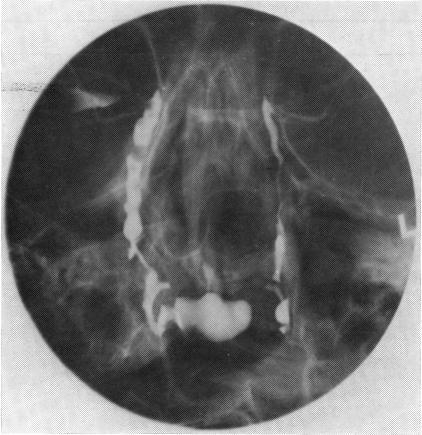

Fifty-one patients were investigated by subtraction macrodacryocystography (SMDCG, 103 systems) and by lacrimal scintigraphy (LS, 105 systems). It was found that these investigations complemented each other and between them the precise site of obstruction in the lacrimal drainage apparatus could be determined in 80%. The radiation dosage to the lens in SMDCG significant, and it is therefore recommended that the patients with lacrimal obstruction should: (1) have lacrimal puncta dilated with a probe to No. 1 diameter and be forbstruction is still uncertain, then and only then should SMDCG be performed.

51例患者接受了泪囊造影术(SMDCG,103例)和泪道闪烁造影术(LS,105例)检查。发现这些检查相互补充,两者结合可确定80%的泪道阻塞确切部位。SMDCG中晶状体所受辐射剂量显著,因此建议泪道阻塞患者:(1)用探针将泪点扩张至1号直径,并在阻塞部位仍不确定时,才应进行泪囊造影术。

然后,只有在这种情况下才应进行SMDCG。